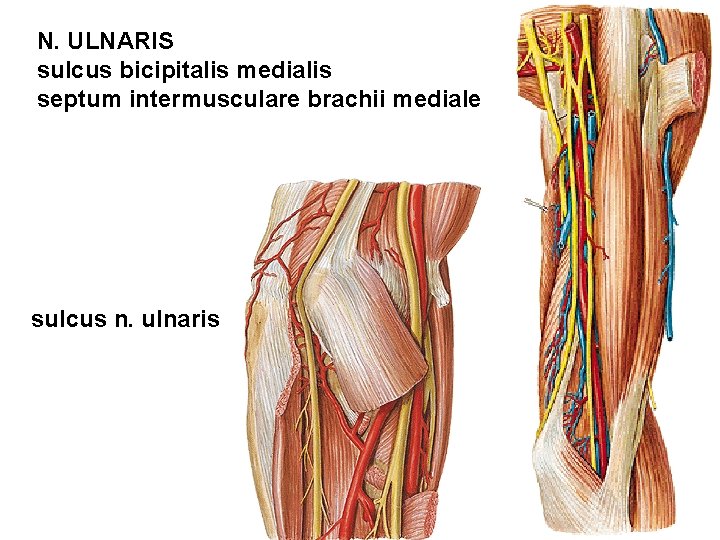

N. ULNARIS sulcus bicipitalis medialis septum intermusculare brachii mediale sulcus n. ulnaris